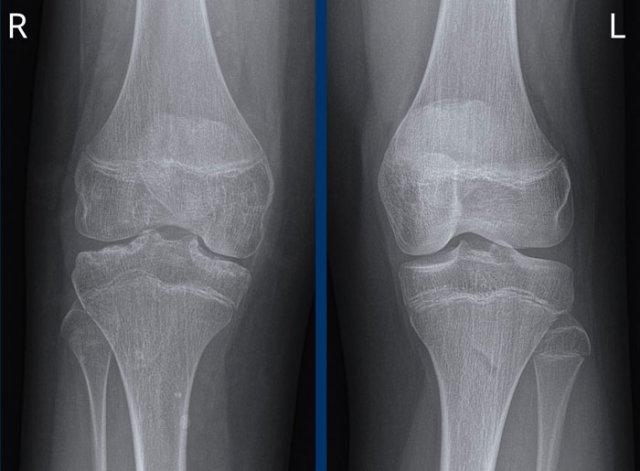

Tại khớp gối, thoái hóa khớp được phân loại theo thang điểm Kellgren và Lawrence.

Thang phân loại này có thể được áp dụng để đánh giá mức độ thoái hóa ở các khớp khác, tuy nhiên nó được thiết kế chủ yếu cho khớp gối.

Thoái hóa khớp gối

Hẹp khe khớp đùi-chày khoang trong mức độ vừa đến nặng, không đối xứng, kèm hình thành gai xương và xơ cứng xương dưới sụn (phân loại Kellgren-Lawrence độ 3-4).